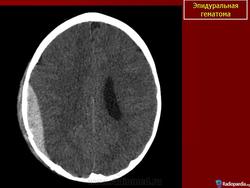

Эпидуральные гематомы - это кровоизлияния, локализующиеся между костью черепа и твердой мозговой оболочкой. Этот тип кровоизлияний чаще встречается у мужчин (M:Ж= 4,5:1). Обычно Эпидуральные гематомы локализуются в височной и теменных областях (60 - 70 %) в зоне перелома кости черепа. Иногда Эпидуральные гематомы встречаются в задней черепной ямке и на основании черепа.